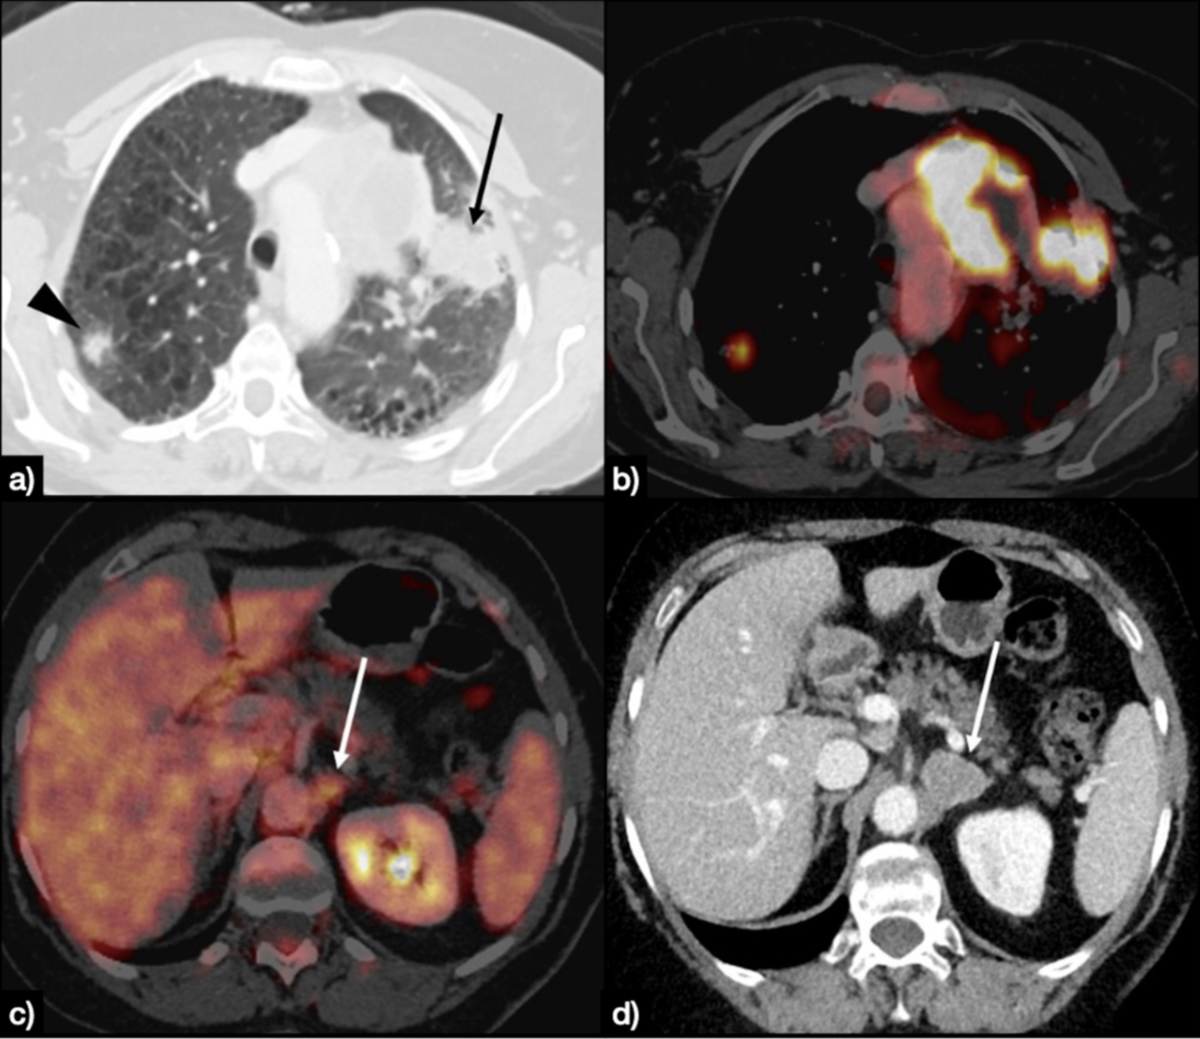

Several meta-analyses demonstrate high sensitivity (ca. 90%) and overall good specificity (ca. 78%) of fluorodeoxyglucose F 18 (18F-FDG) (PET/CT for the assessment of unclear lung lesions [17–19]. The diagnostic accuracy of the PET/CT is strongly positively associated with the intensity of 18F-FDG uptake in lesions [20]. The sensitivity is also higher for larger lesions (e.g. ca. 96% for lesions larger than 10 mm) [21] and vice versa. Small malignant lesions at the boundaries of the spatial resolution of PET scanners (2–6 mm, depending on the performance of the scanners) are often rated false-negatively [22]. The same applies to malignant lesions with low 18F-FDG uptake such as bronchoalveolar cell carcinoma or carcinoid tumours. The lower rates of specificity are caused by accumulation of 18F-FDG in reactive and inflammatory tissues. Whole-body 18F-FDG PET/CT is a powerful method for the detection of lymph nodal or distant metastases of non-small cell lung cancer (NSCLC) and, in this regard, is superior than CT alone (figure 2).

Figure 2Large solid mass of the left upper lung (black arrow), with concomitant contralateral nodule (black arrowhead) (A), fluorodeoxyglucose (FDG)-avid on PET-CT (B). PET-CT also raised suspicion of a lesion in the left adrenal (white arrow in panel C), that was confirmed as an adrenal lesion at the subsequent CT scan, as an enlargement of the gland (white arrow in panel D).

Different meta-analyses show a sensitivity of 74–85% and a specificity of 85–92% for differentiation between a N0–1 status and a N2–3 status [18, 23–26]. The sensitivity and specificity of the 18F-FDG PET/CT for metastases of non-small cell lung cancer in CT-morphologically non-suspicious lymph nodes are 70% and 94%, respectively [25]. In a randomised prospective clinical trial, futile surgical treatments could be reduced by 50% when 18F-FDG PET/CT was performed prior to the surgical intervention [27]. Another clinical trial demonstrated that the number of invasive tests, especially of mediastinoscopies and thoracotomies, is significantly reduced by prior 18F-FDG PET/CT [27, 28]. For the detection of distant metastases of non-small cell lung cancer in 18F-FDG PET/CT, a meta-analysis revealed a sensitivity of 93% and a specificity of 96% [29]. The majority of distant metastases are found in osseous structures and the adrenal glands [20]. Since brain tissue shows a physiologically high 18F-FDG uptake, the sensitivity for the detection of brain metastases with 18F-FDG PET/CT is significantly reduced [30]. 18F-FDG PET/CT is frequently able to identify additional sites of small cell lung cancer (SCLC) thereby changing the tumour stage from “limited disease” to “extensive disease” [31, 32].